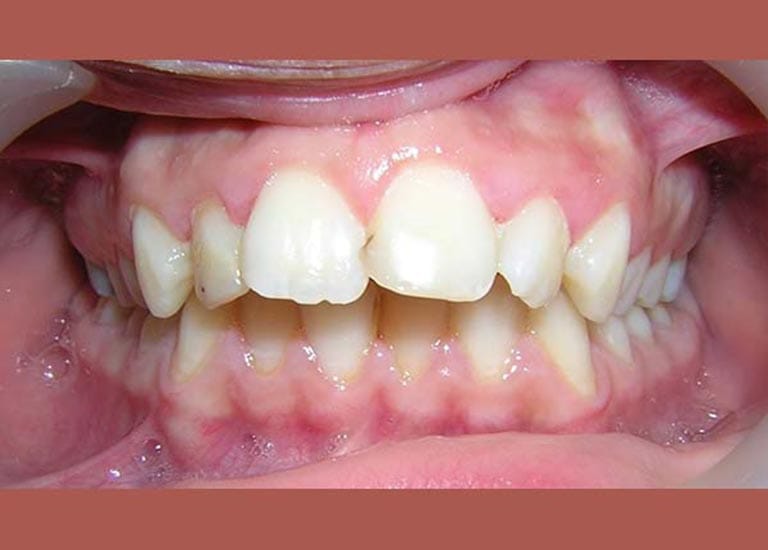

BEFORE

This young man visited me due to the severe protrusion in his teeth. Upon examination, I noticed the presence of molars with large fillings, which are not expected to endure for a long time.